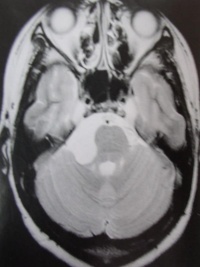

2.MR表现:

①鞍上池或桥小脑角池类圆形或不规则病变,边缘锐利。

②T1加权绝大部分为均匀的低信号,少数由于瘤体内含液态胆固醇或出血而呈高信号影。T2加权呈明显的、均匀一致的高信号影,高于脑脊液信号。

③肿瘤包膜于T1加权呈中等信号,T2加权呈高信号影。

④增强检查无强化效应。

3、CT和MRI扫描 CT见瘤体为边界清楚、形态不规则、呈均匀的低密度影,少数为混杂密度。增强后无强化。MRI在T1加权上表现为略高于脑脊液的低信号影,T2加权上为略低于脑脊液的高信号。注射增强剂后囊肿无强化为其特征。